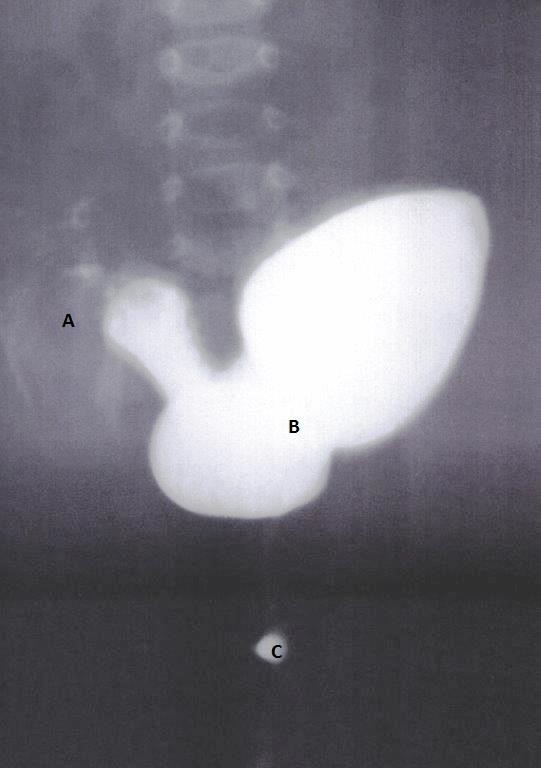

Figure 1: A terminal ileum filled with contrast, B contrast study depicting the huge dilated pouch colon, C contrast medium drop in the region of anal dimple, B/C distance demonstrated between pouch colon and deposit of contrast medium localized at the area of anal dimple.